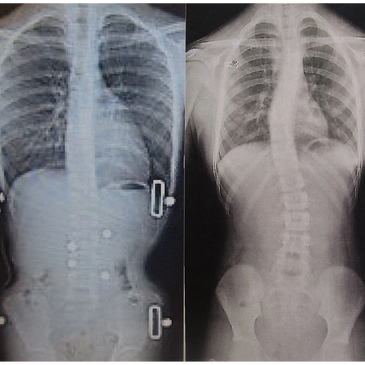

Our goal is to correct the spinal curves as much as possible while wearing the custom spinal brace. This is an example of curve correction while wearing a custom scoliosis brace from Chicago Pediatric Orthotics. The left x-ray is while wearing the TLSO and the right is without. Near 100% correction is noted.

Traditional practices define brace success as having the curves not get worse. Our goal, and clinical observation, is that significant improvements will be seen with brace compliance, younger age when starting brace treatment, scoliosis specific exercise program, and participation in regular physical activities, sports or dance.